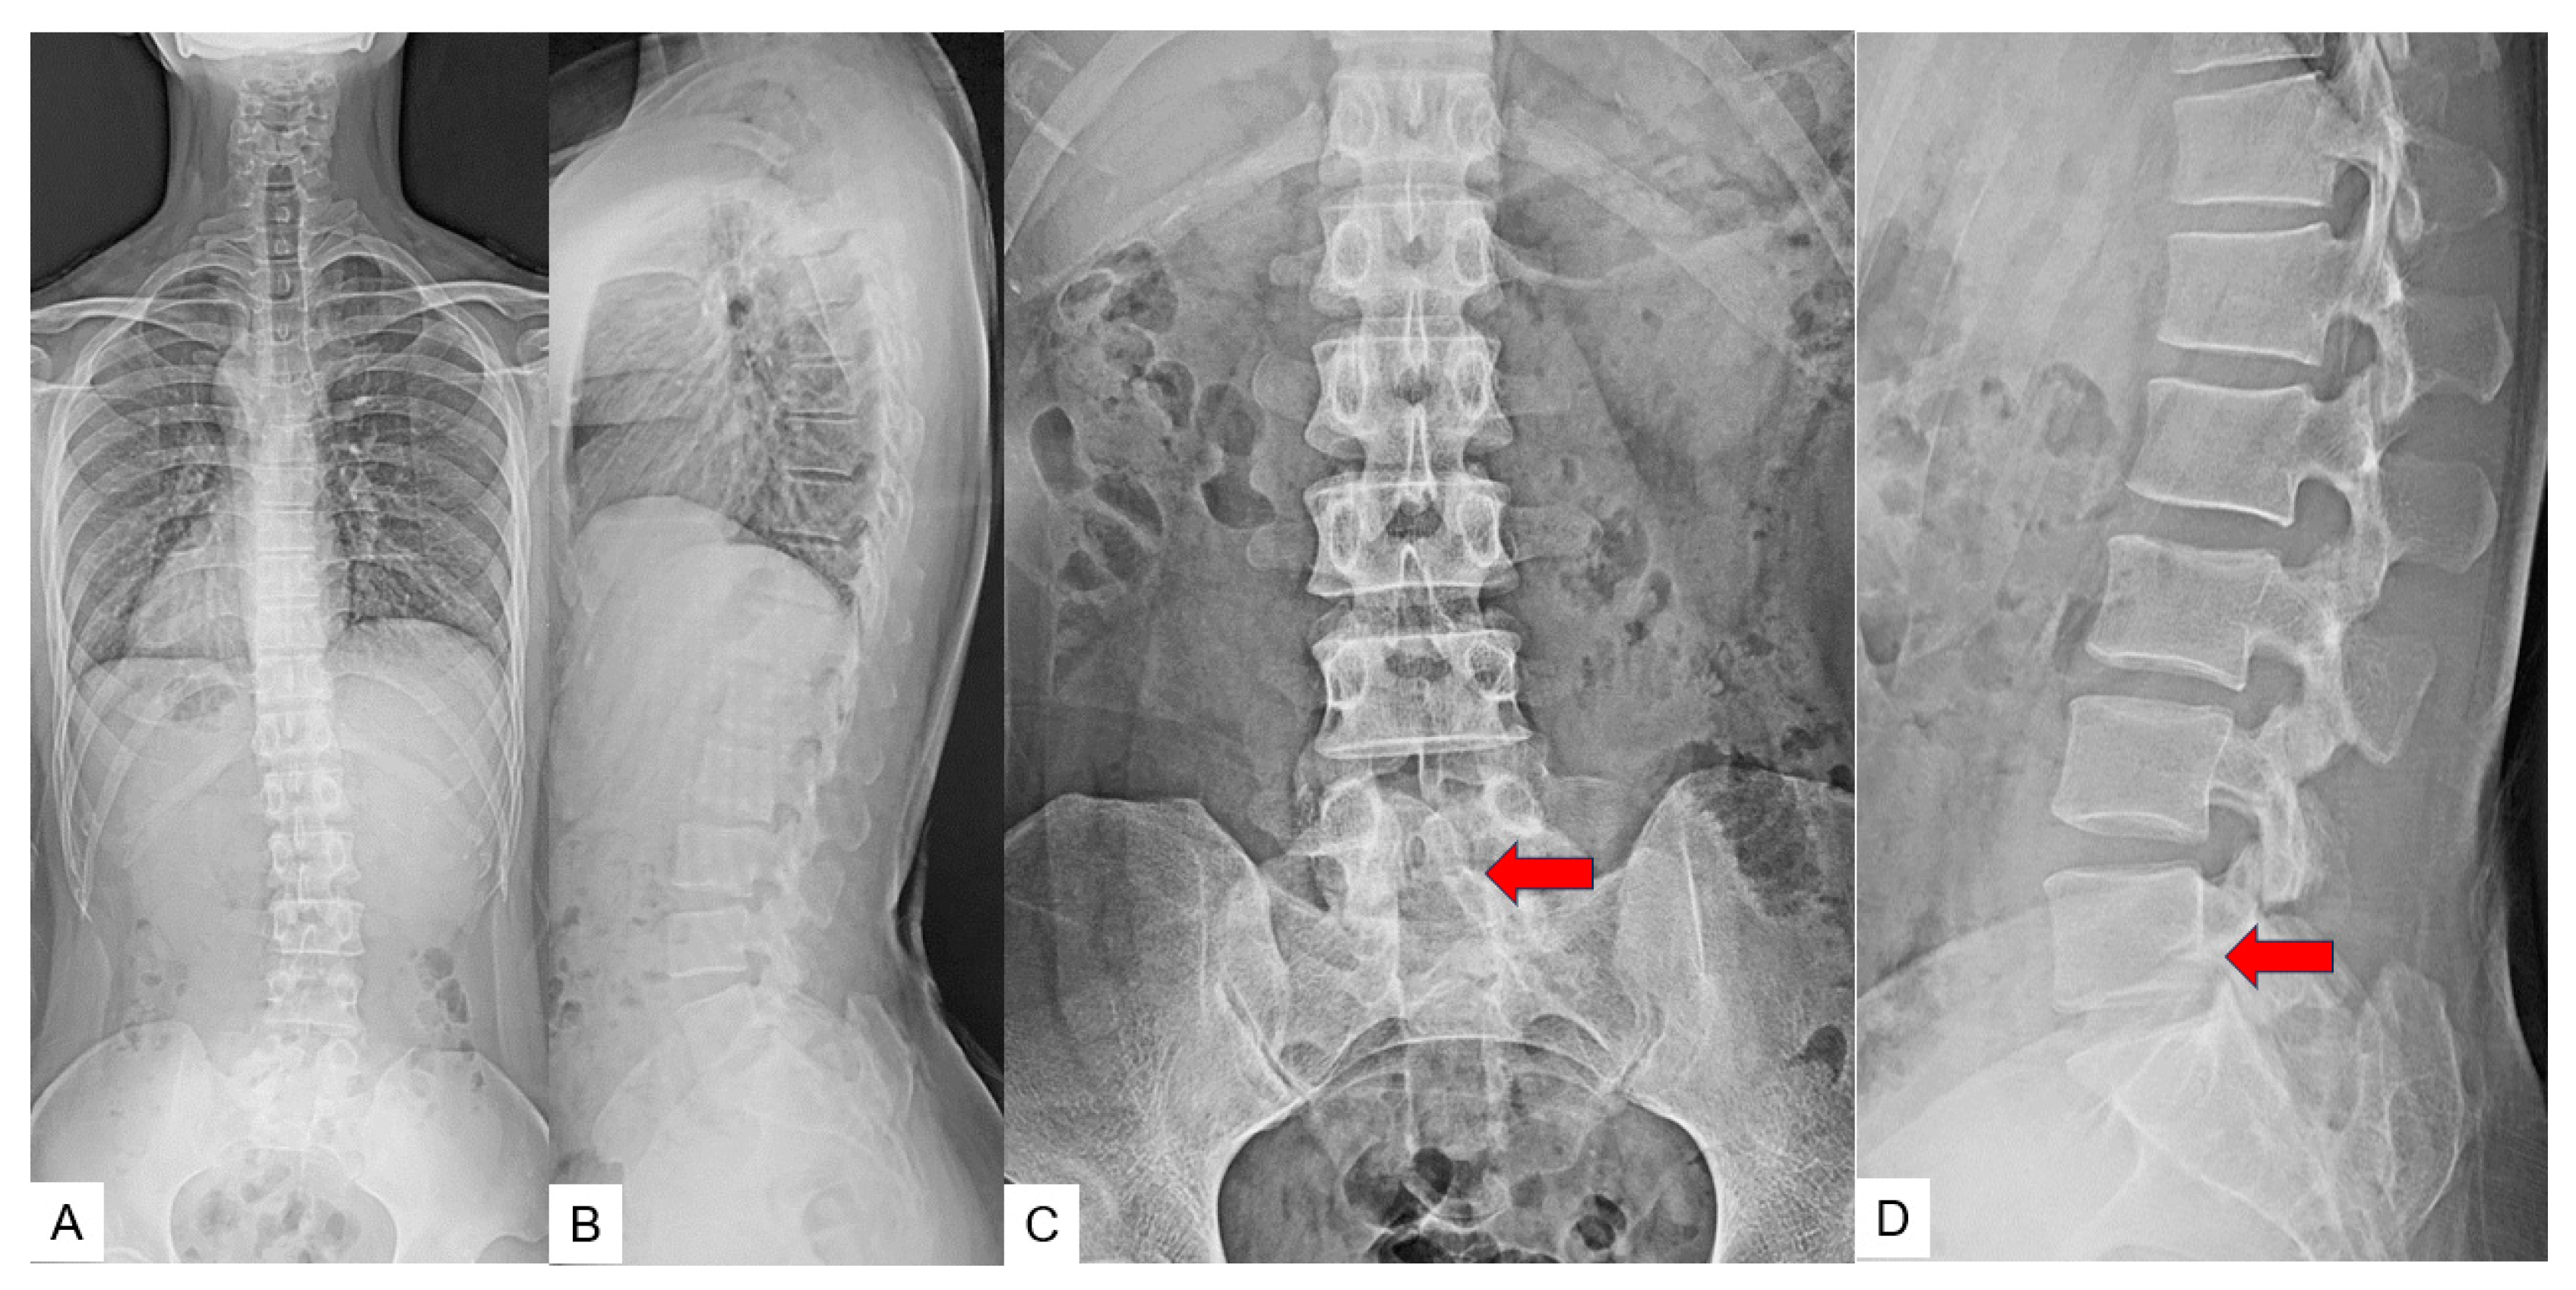

2.3. Preoperative Imaging

3. Case 2: 33-Year-Old Male, Tethered Cord Syndrome, Conventional Technique